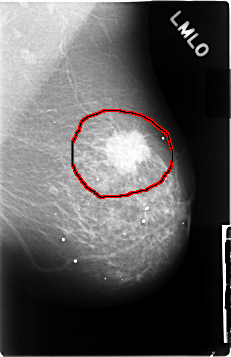

C_0028_1.LEFT_MLO

FILE: C_0028_1.LEFT_MLO.OVERLAY

TOTAL_ABNORMALITIES 1

ABNORMALITY 1

LESION_TYPE MASS SHAPE IRREGULAR MARGINS SPICULATED

ASSESSMENT 5

SUBTLETY 5

PATHOLOGY MALIGNANT

TOTAL_OUTLINES 1

BOUNDARY